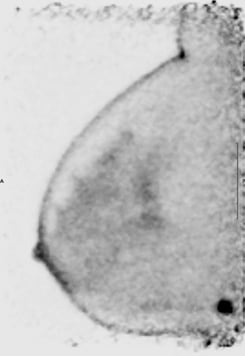

This image shows focal uptake suspicious for malignancy in the posterior breast near the chest wall.

We have found patients tolerate PET mammography very well. We take four images that are eight minutes each (two of each breast). Due to the lengthy acquisitions, the patient is seated in a chair for imaging. This makes positioning more challenging for the technologist due to belly fat which is pushed upward against the bottom of the breast when seated. In traditional mammography the patient stands, which allows the belly fat to fall toward the pelvis and makes it easier to position the inferior paddle. There is a significant learning curve for the technologist for proper positioning of the breast. Additionally, lesions against the chest wall are difficult to image due to the dead space of the detectors.